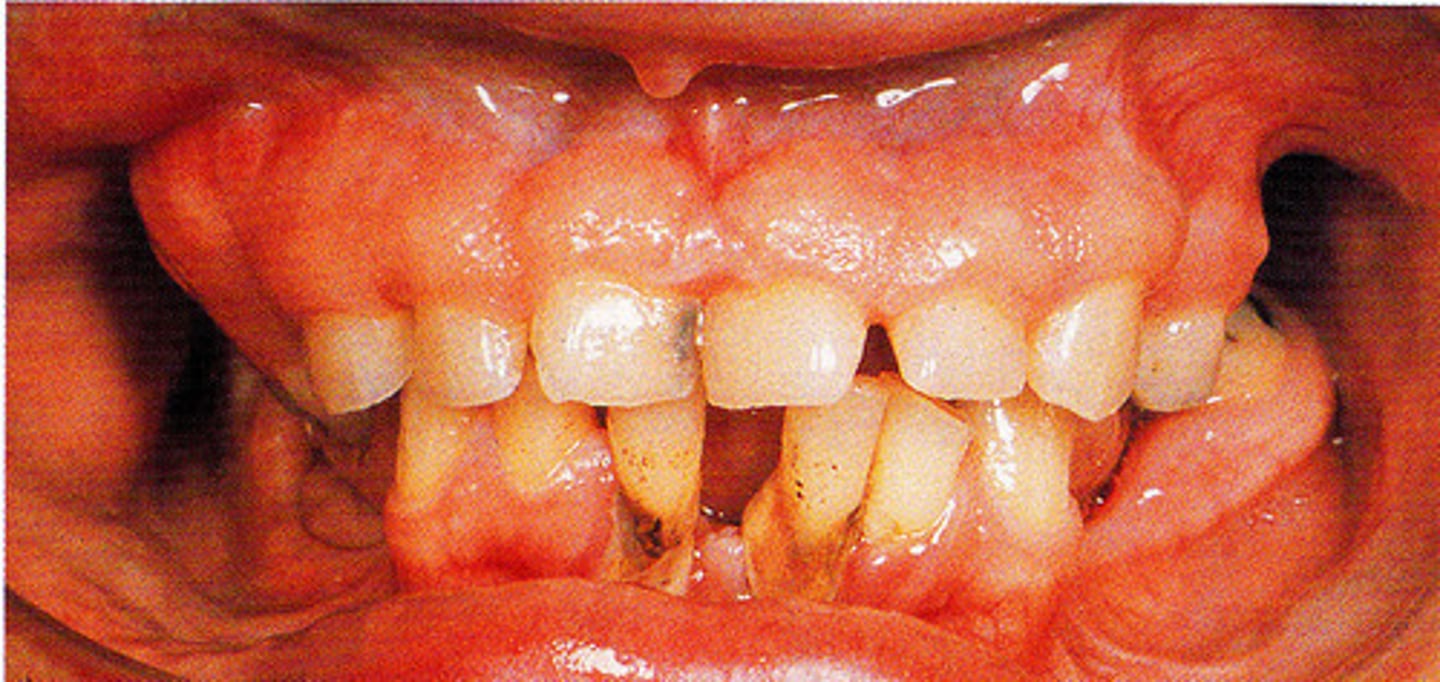

Papillon-Lefèvre Syndrome

At about what age does an individual with Papillon-Lefèvre Syndrome develop a gingivoperiodontal inflammatory process.

1.5 - 2 years of age